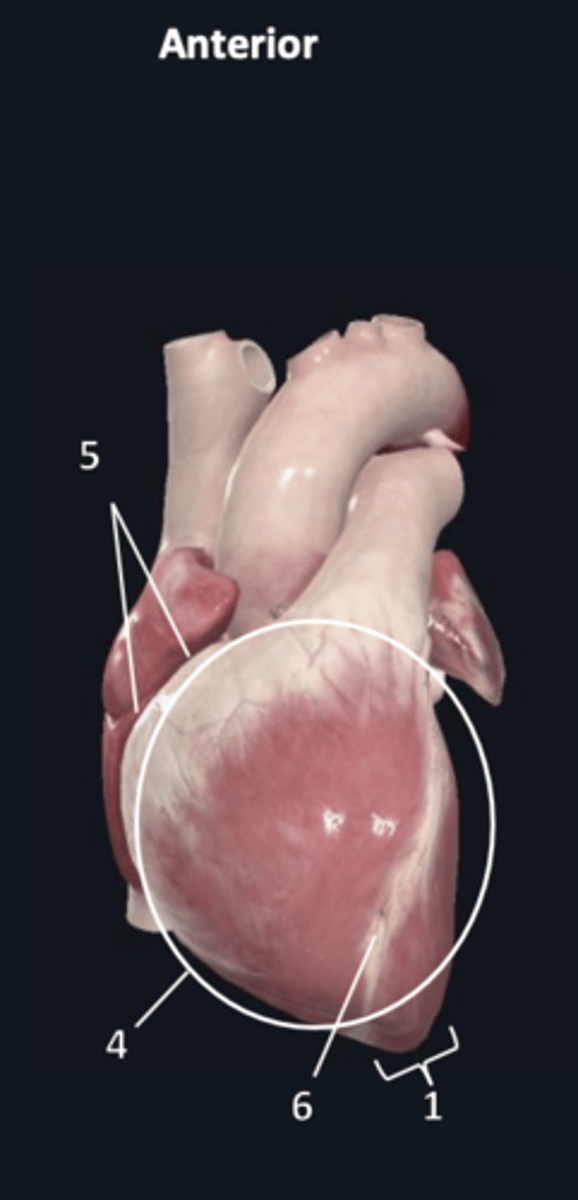

sternocostal surface

4

atrioventricular groove

5

anterior interventricular sulcus

6